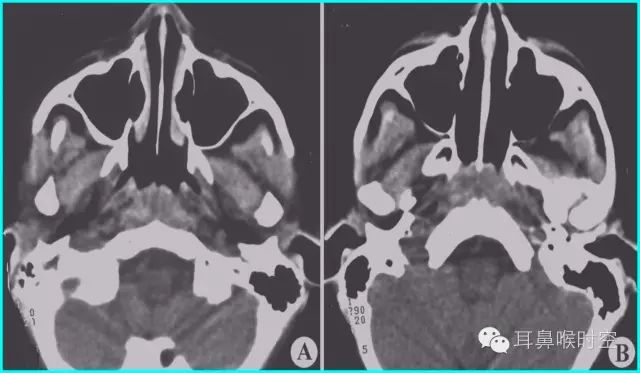

(1)鼻咽腔层面:

标准CT 轴位像:

鼻咽气腔形态因层面不同而不同,其中,呈梯形(图3),长方形(图4)。

咽隐窝及咽鼓管咽口清晰或隐约可见,双侧对称,鼻后孔大部分畅通,咽旁间隙清晰,邻近骨质无破坏。

鼻咽气腔形态

梯形 长方形